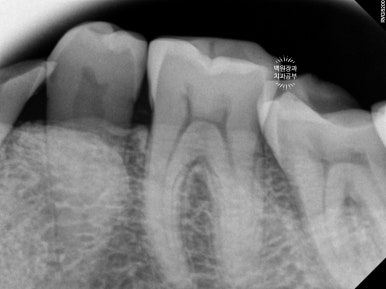

왼쪽 아래 어금니들의 신경치료가 훌륭하게 성공적으로 진행되었습니다.

의도적 근관치료 (intentional root canal treatment)라고도 합니다.

오른쪽 아래 어금니들도 성공적으로 근관치료를 마쳤습니다.

신경치료를 마친 치아들은 통증을 느끼지 않는 상태가 되므로, 정출된 양을 모두 삭제하여 씌워도 아프지 않게 됩니다. 저희 환자분 같은 경우 치아 주변 치조골의 상태는 매우 양호하였으므로 의도적 근관치료를 동반한 보철치료를 선택한 것이 아주 적절하다고 볼 수 있지요.